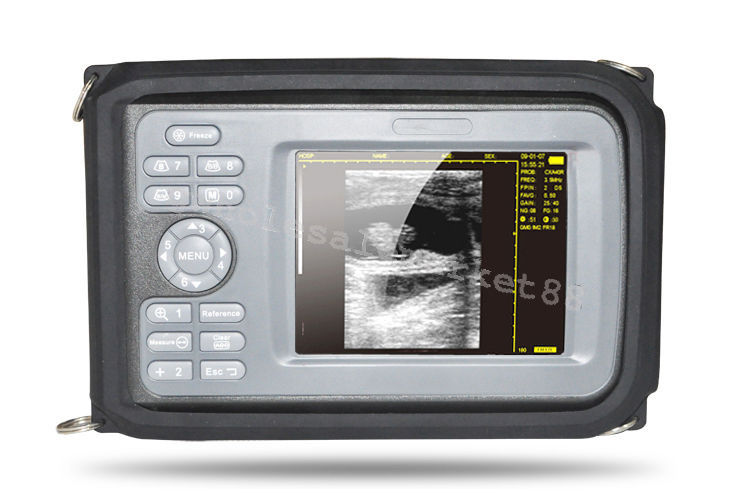

Versatile Functionality and High Precision

The laptop ultrasound scanner is designed for versatility and ease of use. It features both Convex and Transvaginal probes, allowing for comprehensive examinations in various settings. This scanner ensures high precision in imaging, giving healthcare providers the ability to make accurate diagnoses quickly. Because of its ergonomic design, it's easy for practitioners to operate, so they can achieve clear images with minimal effort.

Portability and User-Friendly Interface

One of the standout features of this laptop ultrasound scanner is its portability. Weighing less than conventional ultrasound machines, it allows healthcare professionals to bring it right to the patient’s side. Plus, the user-friendly interface simplifies the operation, making it suitable for medical staff of all experience levels. Also, the compact size ensures that it fits easily into tighter spaces, such as small clinics or in-home care environments.